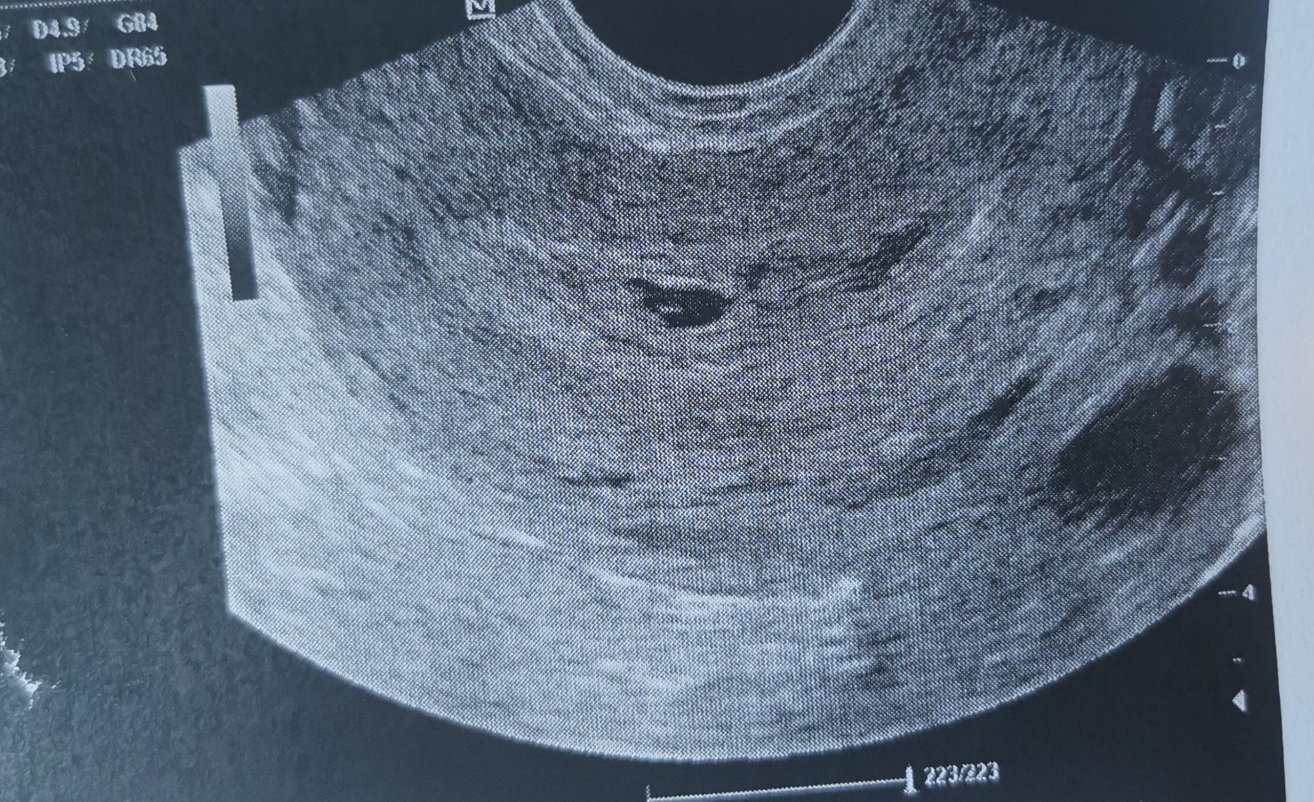

засега 2то мнение ми даде малка надежда, по малко е отколкото трябва, но се вижда нещо в сакчето. Някоя от вас да е не е отговаряла на седмицата, но всичко да е наред? Сакчето е с размер 7мм в 6+2

Да ти кажа, има доста случаи, в които ембрионът се развива по-късно, най-често при късна овулация. Аз когато бях с кухото яйце изчетох МНООГО и имаше доста случаи, в които ембрион и пулс се появяват чак към 9 седмица, така, че винаги има надежда, щом се вижда нещо в сакчето. При мен нямаше нищо, само сак.

Karadzhova88 аз също съм 1 седмица назад. Трябваше да съм в 6+3, а като отидох бях в 5+3, лекарката каза, че всичко е наред, видя се хубаво жълтъчно мехурче и сакче, което беше 1.53см и най-вероятно е заради късна овулация. Сега на 29 съм пак на преглед и се надявам всичко да е наред.

Аз съм в 6 седмица и се видя само сакче 1 см, лекарката каза, че явно съм с късна овулация. Ще видим след две седмици Simple Smile